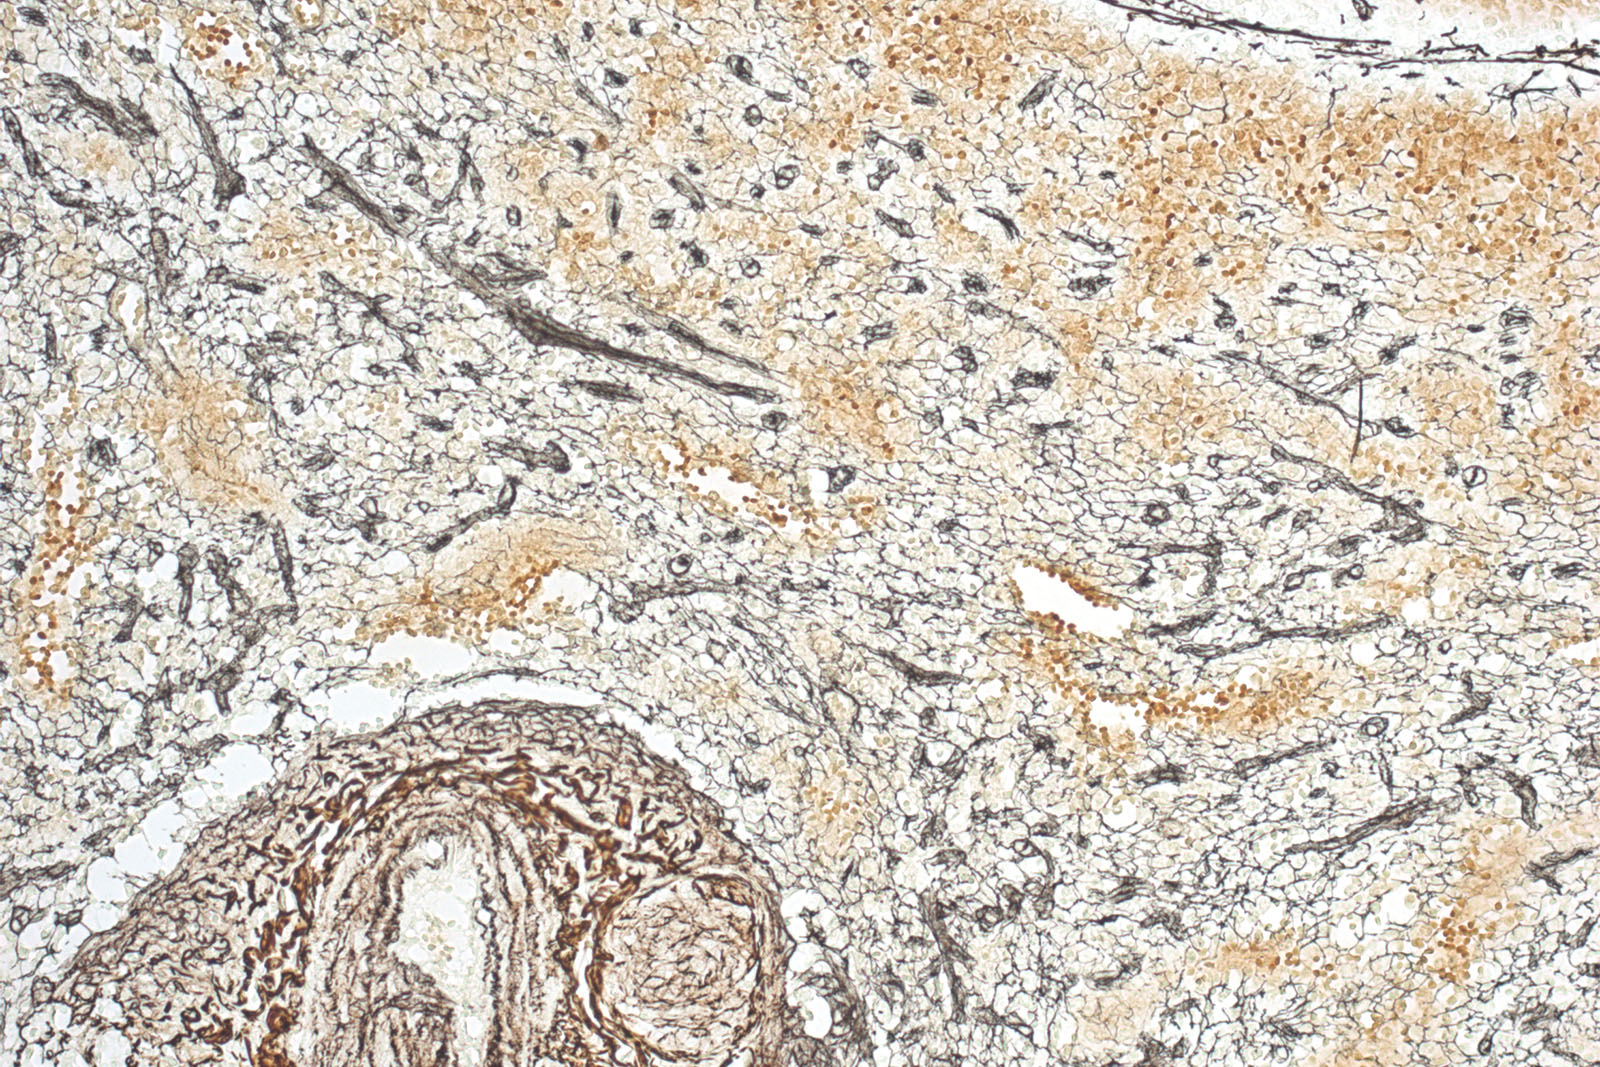

Le kit de réticuline est utilisé pour l'identification et la visualisation plus facile des fibres réticulaires d'argentaffine dans le tissu conjonctif.

La réticuline a une fonction de soutien dans le corps, on la trouve dans le foie, la rate et les reins.

Les fibres de réticuline sont clairement définies avec un foie sain ; le foie nécrotique et cirrhotique a des fibres discontinues. Le test est basé sur des dépôts d'argent sur des fibres de réticuline.

L'échantillon de tissu doit être oxydé avec du permanganate de potassium. L'argent est formé à partir d'une solution d'ammoniac contenant du nitrate d'argent et se dépose sous forme de sédiment brun sur des fibres de réticuline. Le formol agit comme agent réducteur et accélère la procédure. L'argent non lié est lavé et éliminé à l'aide de thiosulfate de sodium.